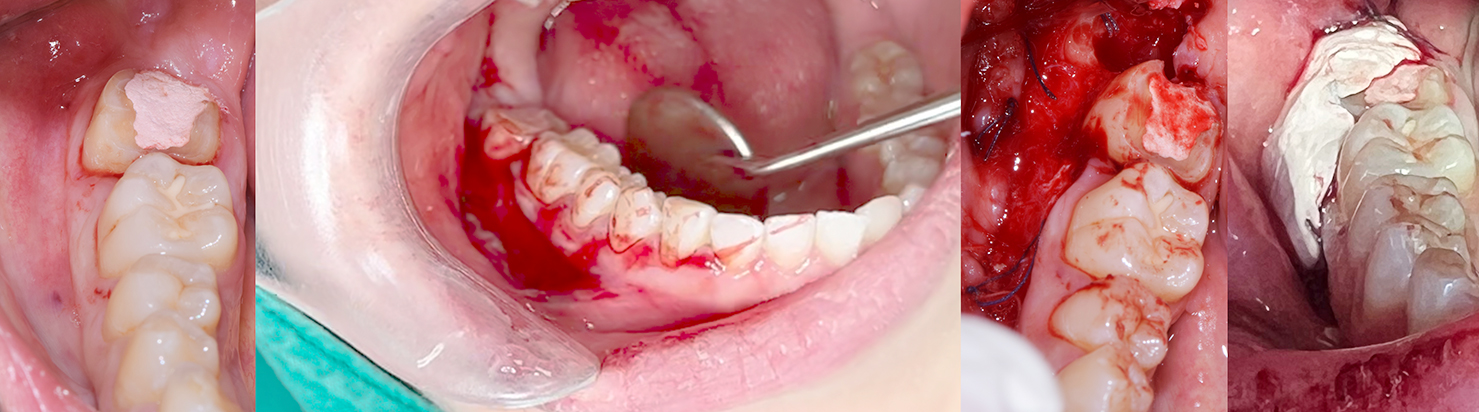

Crown lengthening (Posterior teeth)